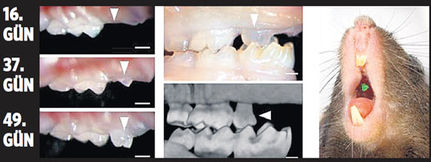

Japonya’nın RIKEN Enstitüsü’nde gerçekleştirilen bir araştırmada, kök hücrelerden diş üretildi. Fareler üzerinde test edilen araştırmada hayvanın dişinden alınan kök hücreleri, başka bir fareye enjekte edildi. Aradan geçen 15 gün sonra ise geliştiği gözlenen hücre ikiye ayrıldı ve diş başarıyla büyümeye devam etti. Araştırmayı yürüten Takashi Tsuji, “Ürettiğimiz dişler, normal bir dişin yarısı büyüklüğünde. Takma dişlerin sonu gelebilir. İleride insanlar üzerinde de başarılı olacağını düşünüyoruz. Özellikle çocuk dişleri için faydalı olacak” ifadelerini kullandı. Bu yöntemle hem dişçi korkusu en aza inecek hem de çürüyen ve çekilen dişlerin yenisi tıpkı süt dişi gibi sağlıklı o larak geri gelebilecek.